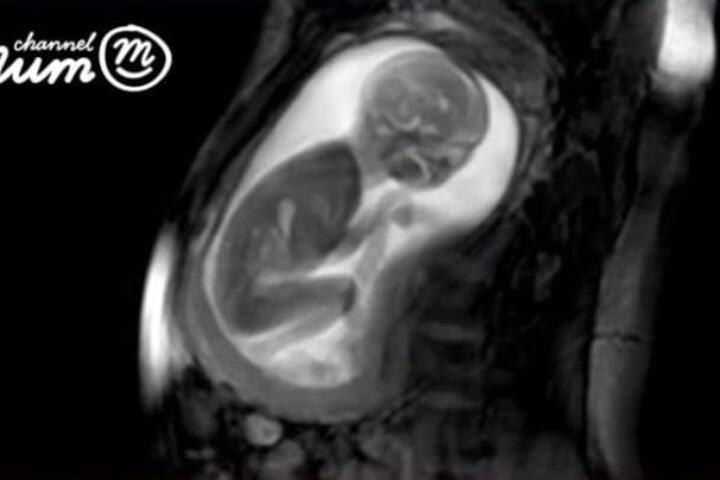

L’ecografia è una importantissima conquista nel campo della ginecologia perché permette di osservare il feto in modo non invasivo per tutta la gravidanza. Oggi esistono anche ecografie 3D (in tre dimensioni) e 4D (in tre dimensioni ma come filmato).

L'ecografia è un importante strumento diagnostico che permette di fornire immagini bidimensionali dell'anatomia fetale. Si chiama ecografia perché utilizza le onde sonore ad alta frequenza per produrre immagini degli organi interni e del bambino che portiamo in grembo.